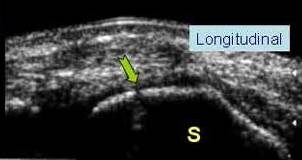

FRACTURA DE SCAFOID

Intreruperea corticalei cu artefact subiacent →

Ligamentul scapulo lunar este continuu

Confirmare radiografica